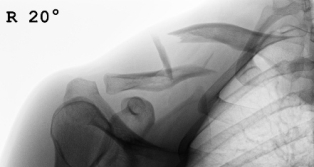

Kompletter Unterarmbruch bei einem 13 jährigen Schüler. Stabilisierung der Speiche und der Elle mit je einem Titanmarkdraht. Die Drähte wurden nach 4 Monaten entfernt.

Kompletter Unterarmbruch bei einem 13 jährigen Schüler. Stabilisierung der Speiche und der Elle mit je einem Titanmarkdraht. Die Drähte wurden nach 4 Monaten entfernt.